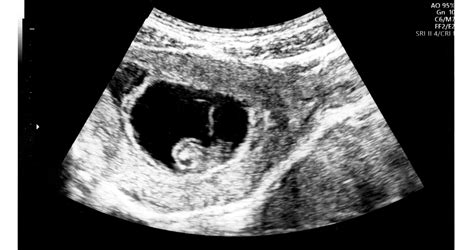

Nemrégiben a pár újra állandóan Magyarországon tartózkodik. Ádám fogtechnikusi szakmája miatt mindig is járt külföldre dolgozni. Bár szerette volna ezt is itthon megoldani, őt Magyarországon mindig csakis színészként kezelték. Aztán amikor Berni várandós lett, rögtön változott is a helyzet, mert a terhességét itt érezte biztonságban, ebben a várandósgondozási rendszerben. Látták, milyen jók a szakemberek és a gépek, különösen itt a Géndiagnosztikán. Persze Ausztria nagyon modern és fejlett, de sajnos valóban körülményesebb volt megoldani a vizsgálatokat. Ráadásul úgy tapasztalták, hogy itthon hihetetlen tüzetességgel történnek a vizsgálatok. Márpedig Berninek erre volt szüksége az első várandósságánál, ami nyolc év várakozás után, az ötödik lombikra sikerült. Arra volt szükségük, hogy az ultrahangos vizsgálatokon nemcsak, hogy lássák, hogyan görbül a haja szála is, hanem ezt részletesen magyarázzák el és mutassák is meg neki. Ezért úgy döntöttek, Berni itthon marad a terhesgondozás idejére, Dr. Imre Ruben doktornál.